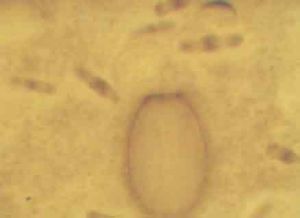

糞便鏡檢發現特徵性的卵囊可確診。需多次糞檢,糞便標本經改良抗酸染色後容易發現卵囊。有時當原蟲處於細胞內期時,只能靠腸組織活檢查才能確診。患貝氏等孢子球蟲病的人,其糞便中常含有由嗜酸性細胞衍化酶夏科-雷登結晶,周圍血常呈現嗜酸性細胞增多症。感染者的腸黏膜活檢可見微絨毛縮短,固有層有淋巴細胞,漿細胞和嗜酸性細胞浸潤。治療